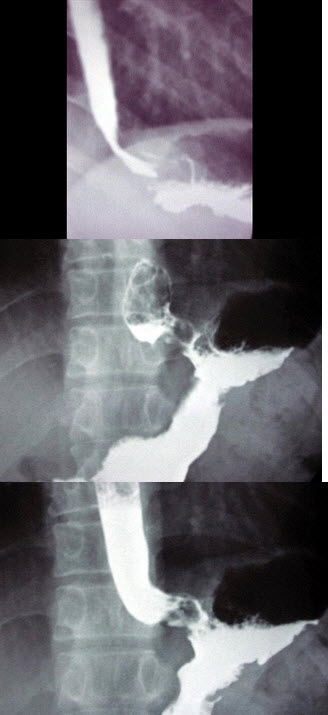

104、单项选择题

男,70岁,进行性吞咽困难半年,结合图像,最可能的诊断为()

A.正常食管

B.食管静脉曲张

C.食管平滑肌瘤

D.贲门失弛缓

E.食管癌

108、单项选择题

女,74岁,上腹痛4月,纳差,结合图像,最可能的诊断为()

A.正常表现

B.胃炎

C.胃癌

D.笔杆征

E.十二指肠占位

143、单项选择题

男,49岁,心前区阵发性绞痛10天。贫血面容,有胃病史。结合图像,最可能的诊断为()

A.胃癌

B.胃小弯溃疡

C.胃炎

D.胃下垂

E.胃窦癌